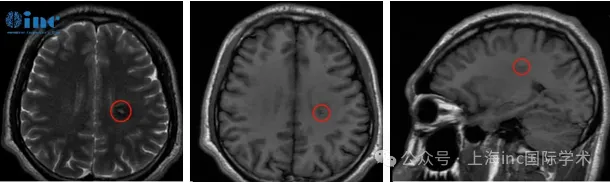

去医院做MRI检查那天,阿勇攥着报告单的手在发抖:左侧半卵圆中心区,长了一个8.0×11.0mm的“类圆形异常信号灶”,医生怀疑是功能区海绵状血管瘤。

2022年5月的MRI报告进一步证实:阿勇的血管瘤正处于急性出血期。这意味着,已经出血过一次,若不及时处理,再次出血可能导致右手彻底瘫痪,甚至影响语言功能。

2022年5月,检查MRI影像,血管畸形处于急性出血期